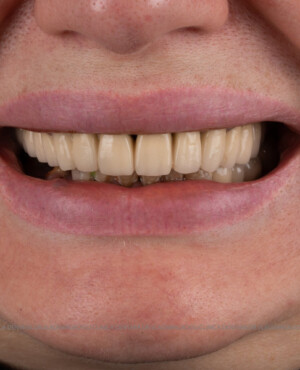

Caz 1

- Posibilitatea realizării unei proteze cu 12-14 dinți, oferind un aspect estetic natural și funcționalitate optimă.

Pentru pacienții cu edentație extinsă sau dinți nefuncționali, metoda All-on-6 oferă o alternativă modernă și eficientă la proteza mobilă, asigurând o restaurare fixă, stabilă și estetică a danturii. Datorită distribuirii optime a implanturilor și a tehnologiei avansate implicate, această soluție îmbunătățește considerabil calitatea vieții, confortul și funcționalitatea orală. Succesul tratamentului depinde de o planificare riguroasă, de utilizarea componentelor de calitate și de competența echipei medicale, ceea ce face ca alegerea unei clinici specializate să fie esențială pentru obținerea unor rezultate durabile și sigure.